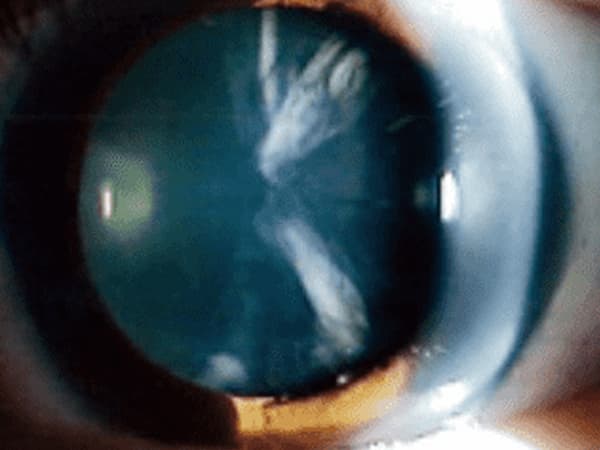

白内障

白内障は、加齢などの原因で、目の中でレンズの役割を果たしている水晶体が白く混濁した疾患です。